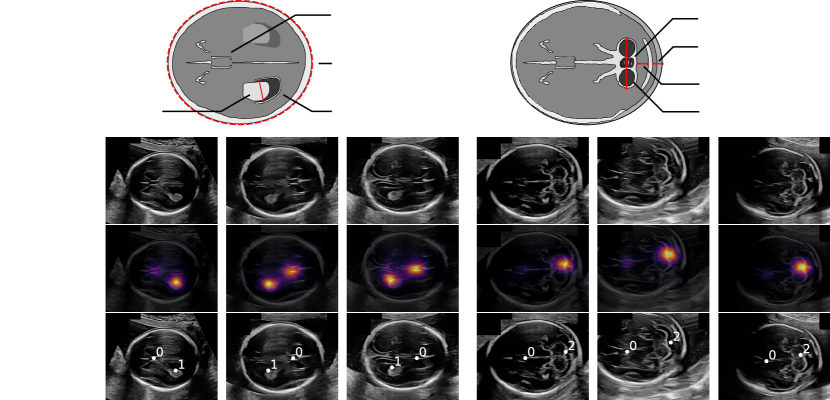

We selected 90 scans to train the saliency predictor and used the remaining 122 scans to evaluate the landmark discovery method. We considered the fetal neurosonographic standard views, i.e., the transventricular (TV) and the transcerebellar (TC) plane (first row in Fig. 2). On the TV plane the operators measure the head circumference (HC) and the lateral ventricle (LV). On the TC plane they measure the transcerebellar diameter (TCD), the nuchal fold and the cisterna magna. The views are defined by the visibility of these structures as well as the appearance of the cavum septi pellucidi (CSP). From the 122 ultrasound scans, we automatically extracted 143 TV and 124 TC plane images by performing optical character recognition on the machine’s graphical interface.

| Head circumference |

| Cerebellum |

| Vermis |

| Ultrasound image |

| Saliency overlay |

| Landmark locations and cluster labels |

| Lateral ventricle |

| Nuchal fold |

| TV |

| TC |

| Choroid plexus |

| Cavum septi pellucidi |

| Cisterna magna |

Salient Landmark Discovery. Fig. 2 shows exemplary results of the salient landmark discovery method. All shown predicted saliency maps have two peaks: one at the CSP and one at the LV (TV images) or at the cerebellum (TC images). The cluster labels correctly match the landmarks across images.